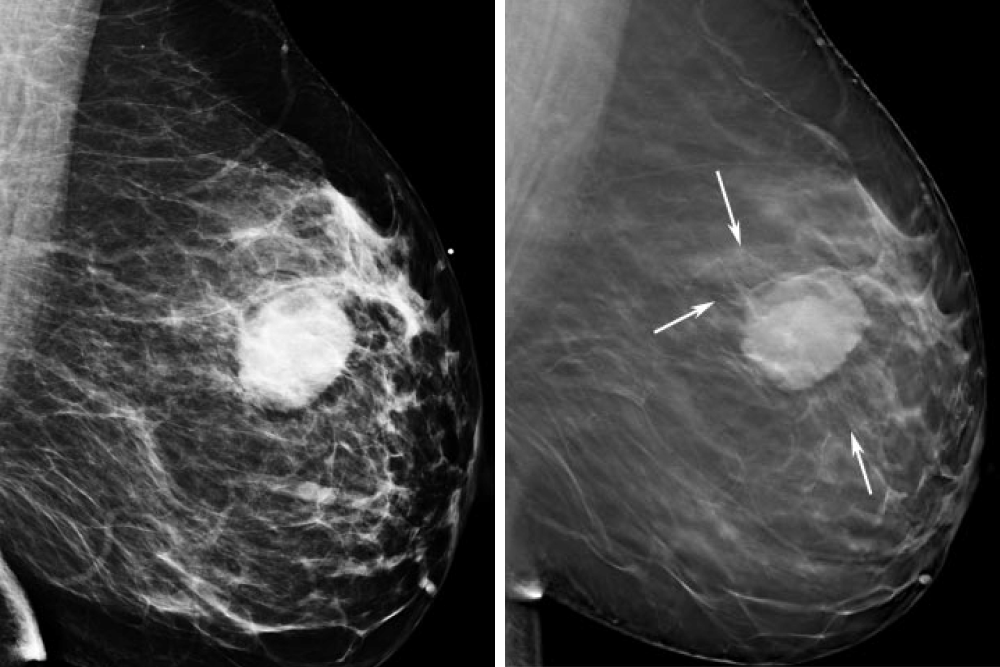

Аномалии молочной железы: медицинские примеры и визуализация

Раздел: Мудрость в деталях